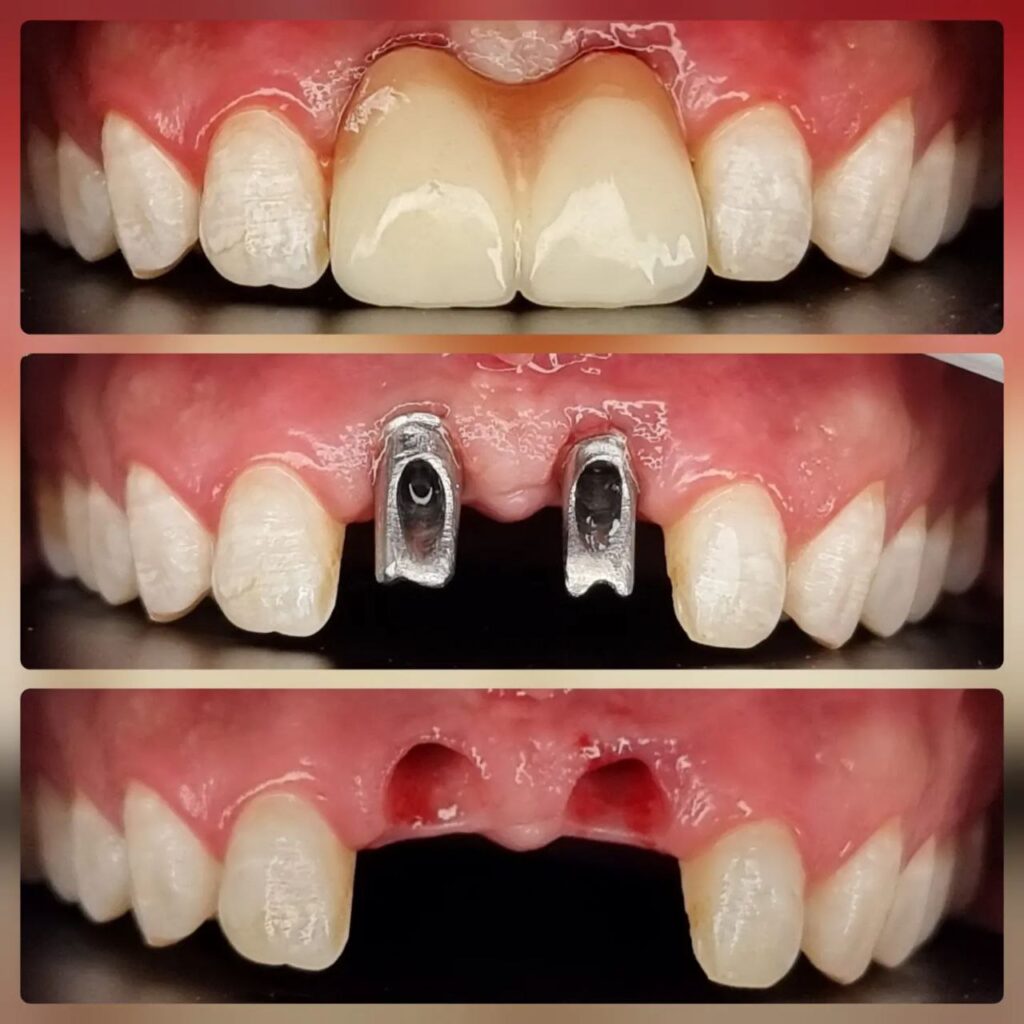

کاشت ایمپلنت دندان

اطمینان حاصل کردن از اینکه دندانهایتان به نحوی زیبا و طبیعی جایگزین شدهاند، از اهمیت بسیاری برخوردار است. ایمپلنت دندان به عنوان یک روش درمانی دائمی در دندانپزشکی شناخته میشود که حاصل آن، یک دندان زیبا و طبیعی در دهان شما خواهد بود.

هرچند که این روش درمانی هزینهی بیشتری نسبت به روشهای دیگر دارد، اما ارزش زیبایی که ایجاد میکند، قابل انکار نیست. ایمپلنتها به قدری شبیه به دندانهای طبیعی هستند که به سختی میتوان آنها را از دیگر دندانها تشخیص داد.